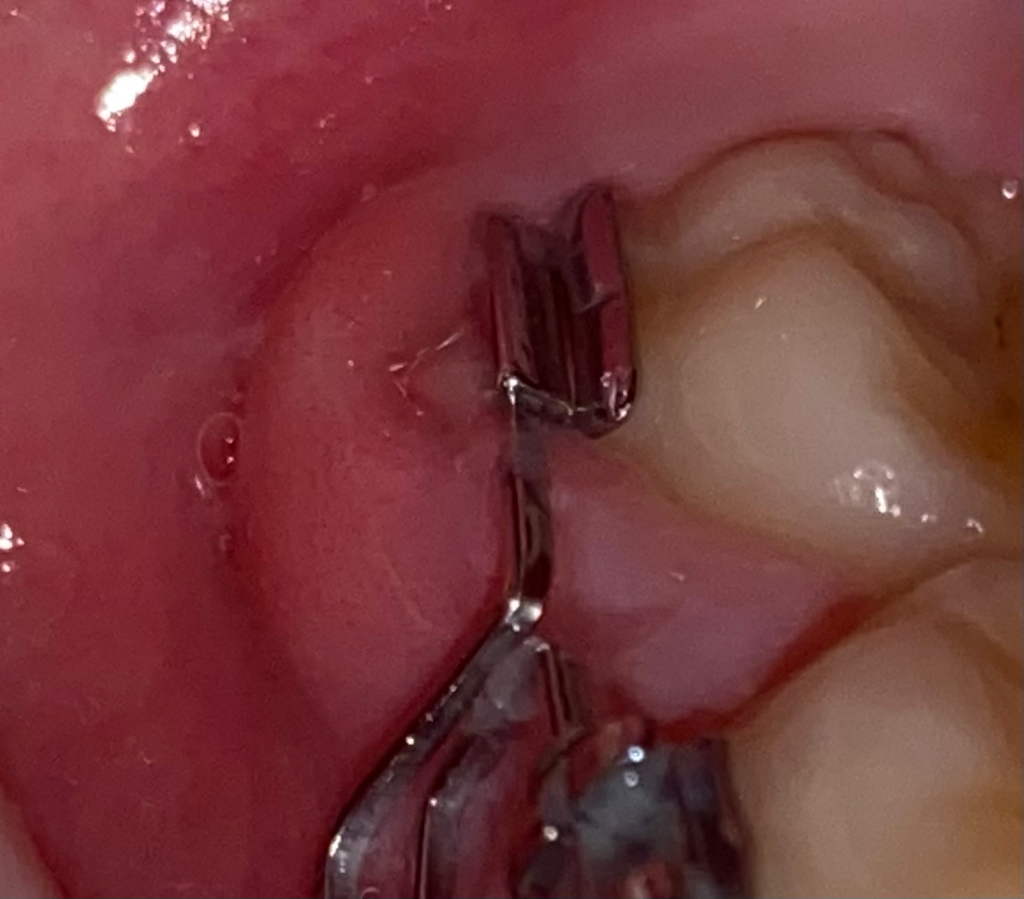

잇몸이 좀 많이 부었는데요 빨리 가라앉히는 방법 있나요?

어제까지만 해도 저만큼 밖에 안 부었는데 아침에 일어나서 보니까 붓다가 교정기에 껴가지고 피도 나더라구요ㅠㅠ 병원 가봐야할까요? 아님 그냥 가라앉게 냅둘까요 잘 자면 가라앉으려나요,,

• 1번 째 사진

• 2번 째 사진

붓는 정도가 계속 심해진다면 치과를 가보시는게 좋겠습니다 . 약처방과 원인파악이 필요해보입니다

해당 부위에 청결 관리가 미흡하거나 자극이 있는 경우 붓기가 발생할 수 있으므로

해당 부위를 청결하게 관리하고 이후에도 붓기가 지속된다면 치과 내원하여 검진 받아보는 것이 좋습니다

잇몸이 많이 부으신거 같습니다. 염증이 생긴거 같은데 치과에 가셔서 잇몸치료를 받으시고 약을 드셔야될것같습니다.